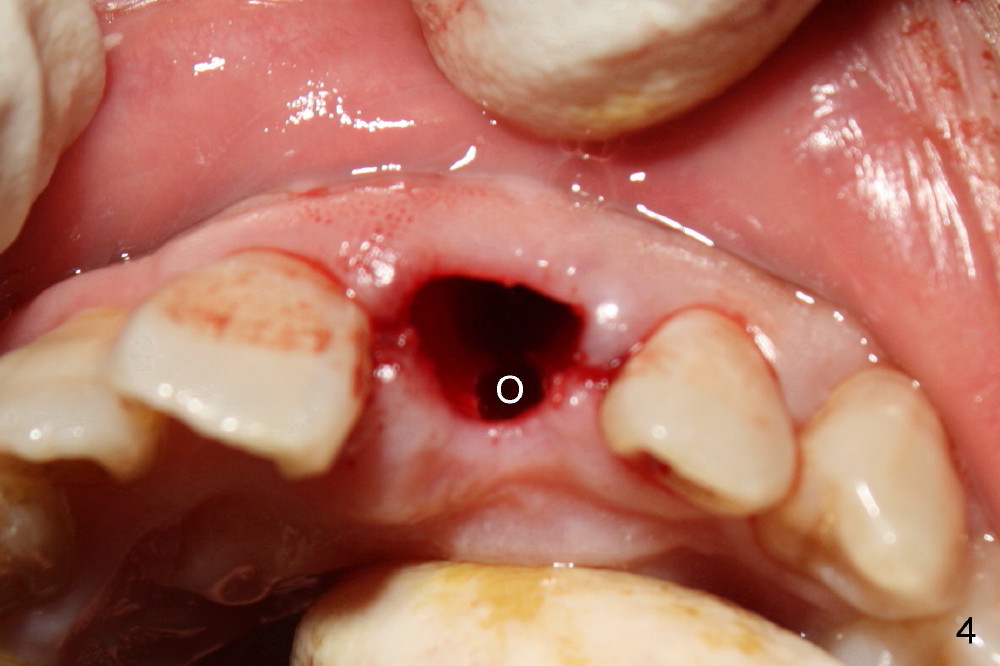

The upper right central incisor (Fig.1: #9) fractures subgingivally due to trauma for a 40-year-old man.  The incisive canal is large (I) and close to the root of the central incisor.  After extraction, the osteotomy (Fig.3b, 4: O) is made with 2 mm pilot drill (Fig.2: D) on the lingual wall (Fig.3a: L) of the socket (Fig.3a: S).  To push the incisive canal mesially, the osteotomy is enlarged by 3.5x21 mm and 4x21 mm tapered osteotomes (Fig.5,6: O).  Due to the lingual slope (Fig.7a arrow), the osteotome (blue outline) starts to deviate bucally.  To reduce this tendency, the coronal portion of the lingual slope is removed (Fig.7b: yellow circle).  The final implant (4.5x20 mm) is able to be placed as lingually as possible (Fig.7c, 8).